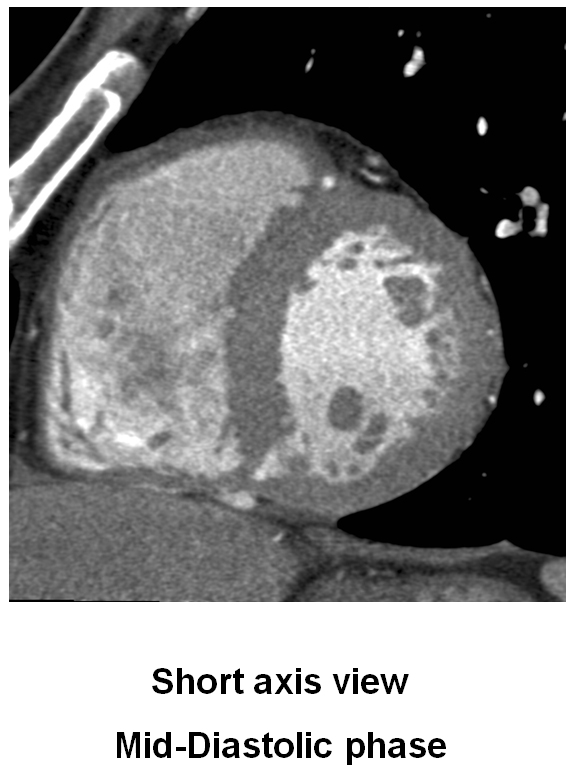

M/60 C.C. Atypical chest pain (since 2months) / Diabetes + / HR at MDCT scan: 70-75 bpm.

CHARY DURAIKANNU, VRR Diagnostics, INDIA

HIT : 82